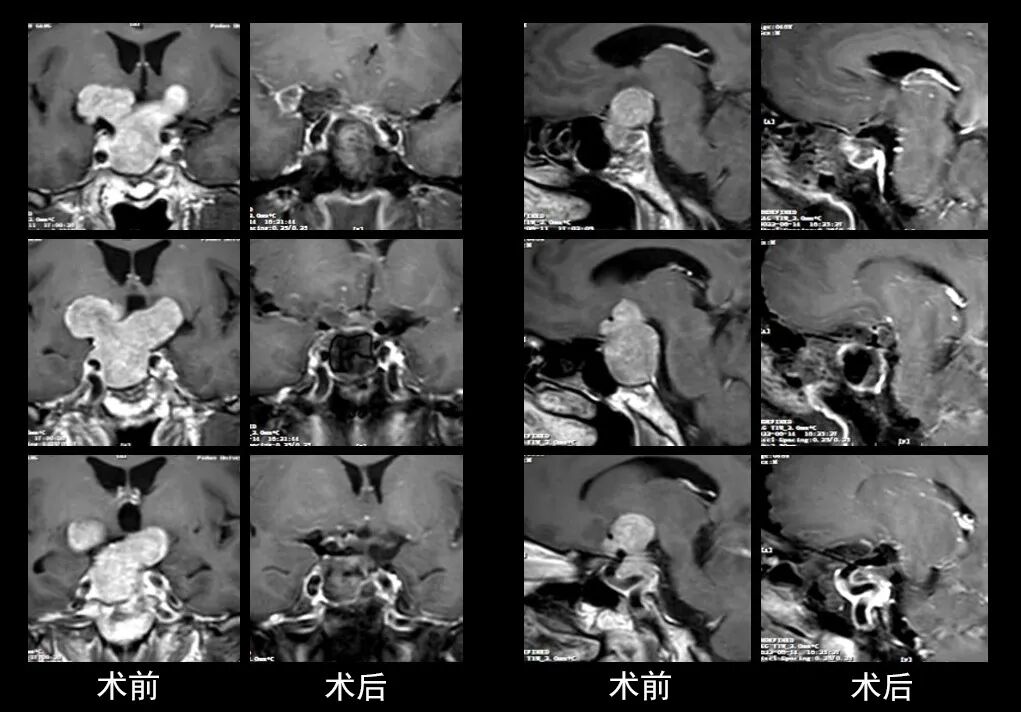

本研究中采用联合手术策略的代表性病例展示:

左右滑动查看更多

图片

case 5

case 6